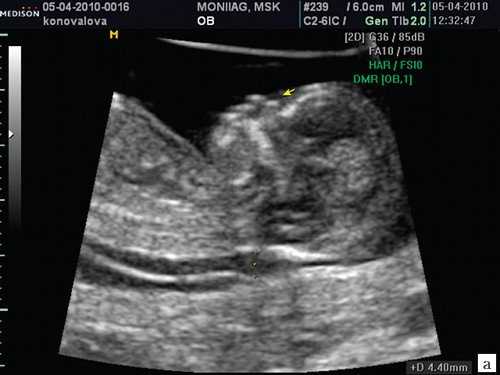

Если все критерии соблюдены, то на уровне носа плода должны быть видны три четко различимые линии: верхняя линия представляет собой кожу, книзу от нее визуализируется более толстая и более эхогенная, чем кожа носовая кость. Третья линия, визуализируемая кпереди от носовой кости и на более высоком уровне, чем кожа - это кончик носа (рис. 1).

Рис. 1. Нормальная носовая кость.

Считается, что носовая кость нормальна, когда она по своей структуре более эхогенна, чем надлежащая кожа и патологична, если она не видна (аплазия) (рис. 2) или ее длина меньше нормы (гипоплазия) (рис. 3). В случае одинаковой или меньшей эхогенности носовой кости чем кожи носовая кость считается патологической (рис. 4).

а) Стрелкой указана эхогенная кожа плода.

б) Стрелкой указано отсутствие носовой кости.